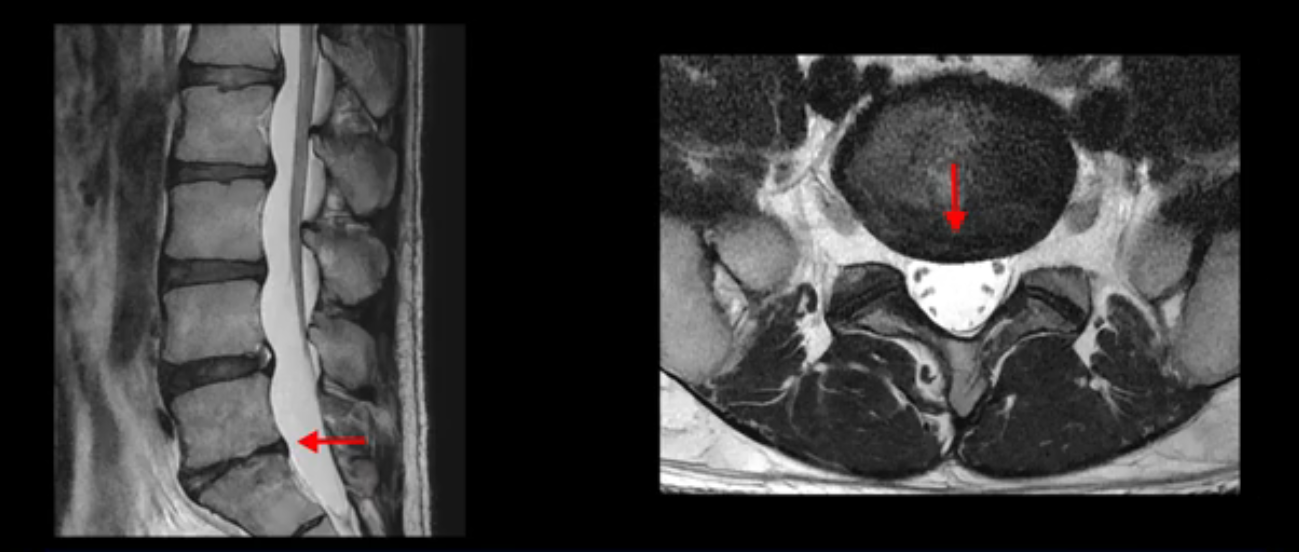

4번 5번은 가운데로 섬유륜이 찢어져서 디스크가 살짝 밀려나와 있지만 역시나 최근에 찢어지고 밀려나온 걸로 판단되지 않고 오래 전에 찢어진 흔적으로 보입니다.

왜 최근에 찢어진 급성이 아니고 오래된 거라고 하는지 이 부분도 뒤에 한꺼번에 설명 드리겠습니다.

앞서 1번 2번, 4번 5번, 5번 1번의 디스크가 찢어지고 조금 밀려 나온 게 최근에 찢어진 게 아니고 오래된 걸로 보인다고 말씀 드렸죠. 왜 그럴까요? 만약 급성으로 찢어진 것이라면 아주 심한 디스크성 통증이 있겠죠. 기침이나 재채기를 하면 심하게 아프고 허리를 조금만 구부리거나 비틀면 아주 날카로운 통증들이 생길 겁니다. 그런데 이분은 이런 증상이 전혀 아닙니다. 또 디스크의 밀려나온 정도도 전혀 심하지 않기 때문에 이분이 가지고 계신 양쪽 다리 저림, 특히 이분은 누워있을 때도 양쪽 발이 발가락까지 쑤신다고 하는데 이정도 디스크 때문에 그런 증상은 생길 수가 없는 겁니다. 이처럼 이분의 가벼운 디스크 탈출은 이미 오래 전에 진행되었고 섬유륜 자체는 이미 아문 상태인데도 디스크내장증을 진단받은 환자들 중에는 본인이 섬유륜 파열 환자라고 끝까지 믿는 분들이 많습니다. 다시 말하지만 디스크내장증이라는 진단을 받은 환자들을 보면 거의 전부 다 섬유륜 파열 증상이 아닙니다. 증상이 완전히 다릅니다. 진단이 애초에 잘못되면 어떤 치료를 받아도 좋아질 수 없습니다.

이분은 어떤 한 병원에서 디스크 내장증 얘기를 들으셨는데요. 여기 보시는 것처럼 4번 5번의 하얀 HIZ(High Intensity Zone)을 보고 디스크 내장증의 근거로 얘기하는 병원들이 있는데,

이 HIZ는 섬유륜이 찢어졌다가 이미 아문 뒤에도 얼마든지 보일 수 있는 흔적일 가능성이 있어서 재채기를 하면 아픈지, 허리를 구부릴 때 날카로운 통증이 생기는가 등의 증상으로 구별해야 하는데 MRI만 보고 HIZ가 보이면 그게 마치 통증의 원인인 것처럼 얘기하는 의사들이 있습니다. 이분 MRI를 자세히 보고 증상을 정말 자세히 들어본 의사가 있었더라면 다른 환자분들처럼 증상과 MRI가 일치하지 않는다는 얘기를 들을 수 있었을 텐데 이분은 그런 얘기는 듣지 못했습니다.